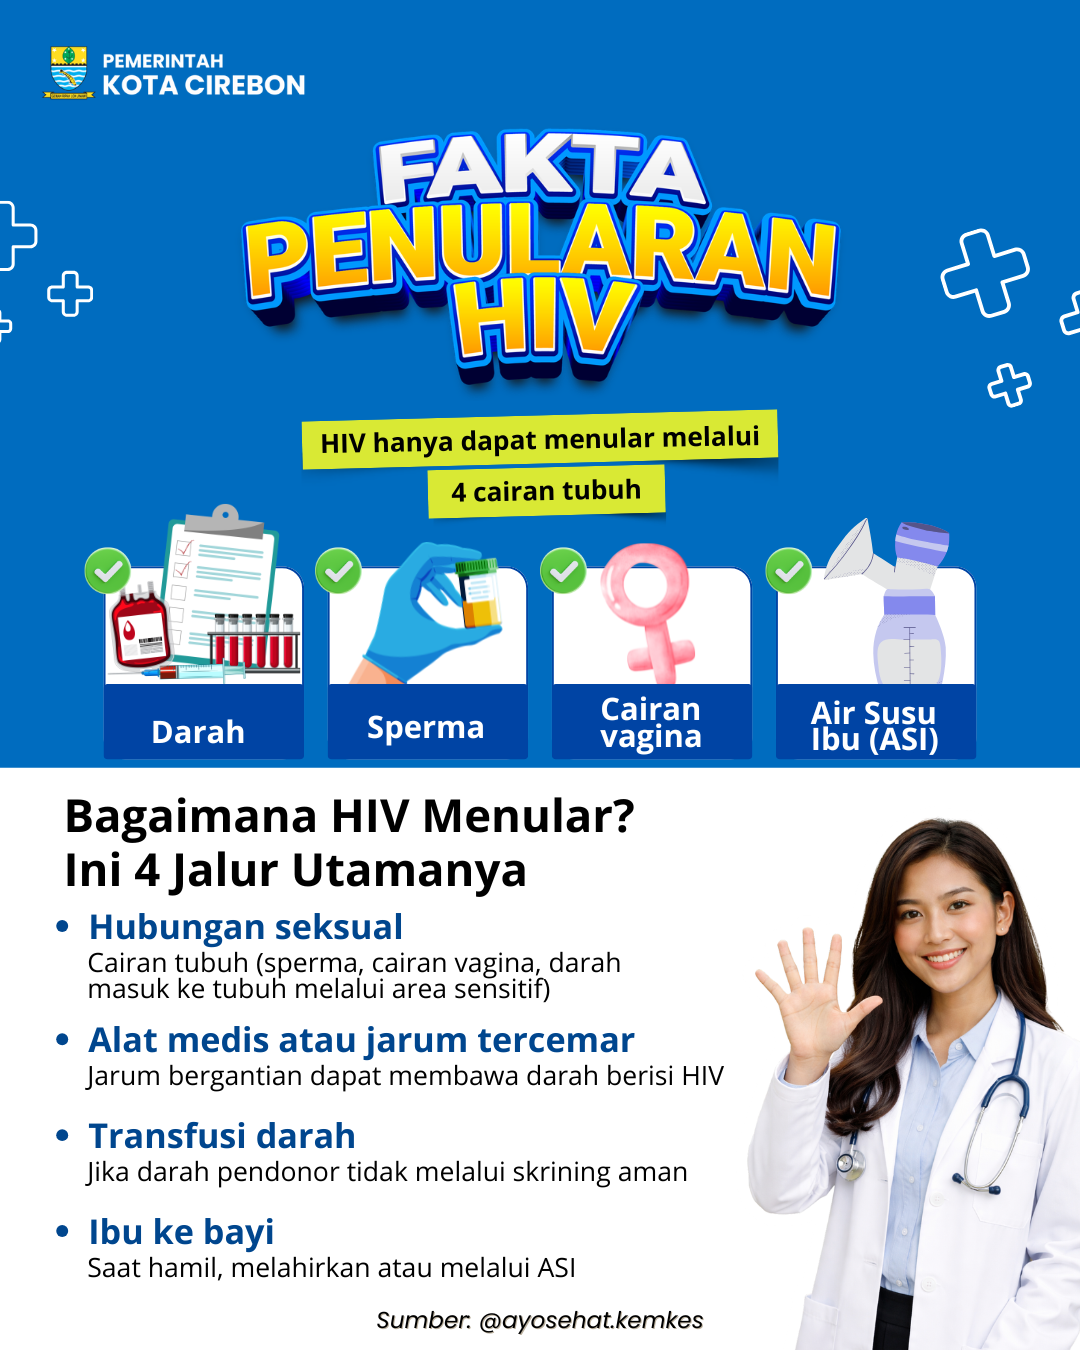

Pemkot Cirebon Ajak Masyarakat Wujudkan Kesehatan Dimulai dari Diri Sendiri

Pemkot Cirebon Ajak Masyarakat Wujudkan Kesehatan Dimulai dari Diri Sendiri